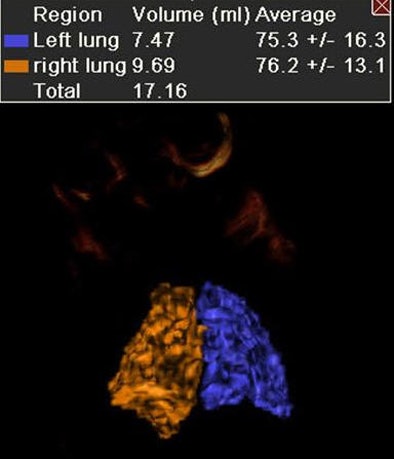

| Above, results showed significantly better survival and less use of ECMO in patients with higher lung volumes. Below, survivors and patients not needing ECMO had significantly higher mean total lung volumes. |

Multiplanar fetal MRI images were acquired on a 1.5-tesla MRI scanner (Signa, GE Healthcare, Chalfont St. Giles, U.K.). All images were reviewed by one of four fetal radiologists; a single technician calculated lung volumes by summation of the right and left lung volumes, minus the volume of the hernia and the mediastinal content, Lee said.

| Above, MRI of left lung (outlined in red) in CDH patient. Below, 3D reconstruction of normal lungs by fetal MRI. All images courtesy of Timothy Lee, MD. |